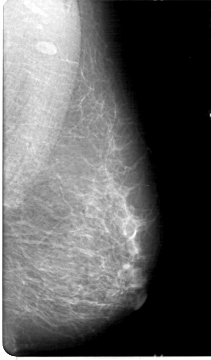

D_4046_1.LEFT_CC

LEFT_CC LINES 5386 PIXELS_PER_LINE 2911 BITS_PER_PIXEL 12 RESOLUTION 43.5 NON_OVERLAY